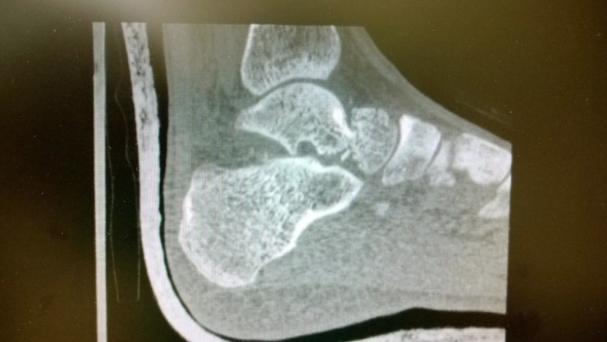

Talar Neck Fractures

• Imaging

• Radiographs

• recommended views

• AP

• lateral

• Canale view

• best view to demonstrate talar neck fractures

• technique is maximum equinus, 15 degrees pronated, xray 75 degrees cephalad from horizontal

• CT scan

• best study to determine degree of displacement, comminution and articular congruity

• CT scan also will assess for ipsilateral foot injuries (up to 89% incidence)